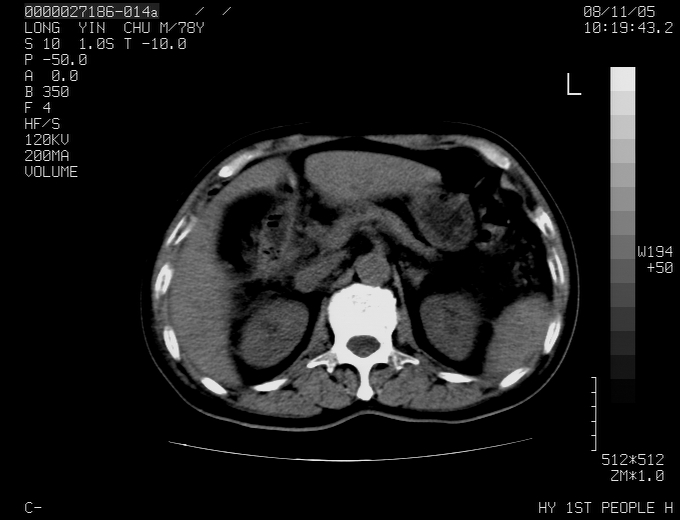

标题: CT16532:M78Y,肝脏病变,请会诊

腹胀,腹痛就诊,男性,78岁,外院b超未见异常。

考虑弥漫性肝癌并脾及双肾转移.双侧胸水.

考虑弥漫性肝癌并脾及双肾转移.双侧胸水.  支持

考虑弥漫性肝癌并脾及双肾转移,双侧胸水。

考虑肝癌并双肾及脾脏转移;双侧胸腔积液。